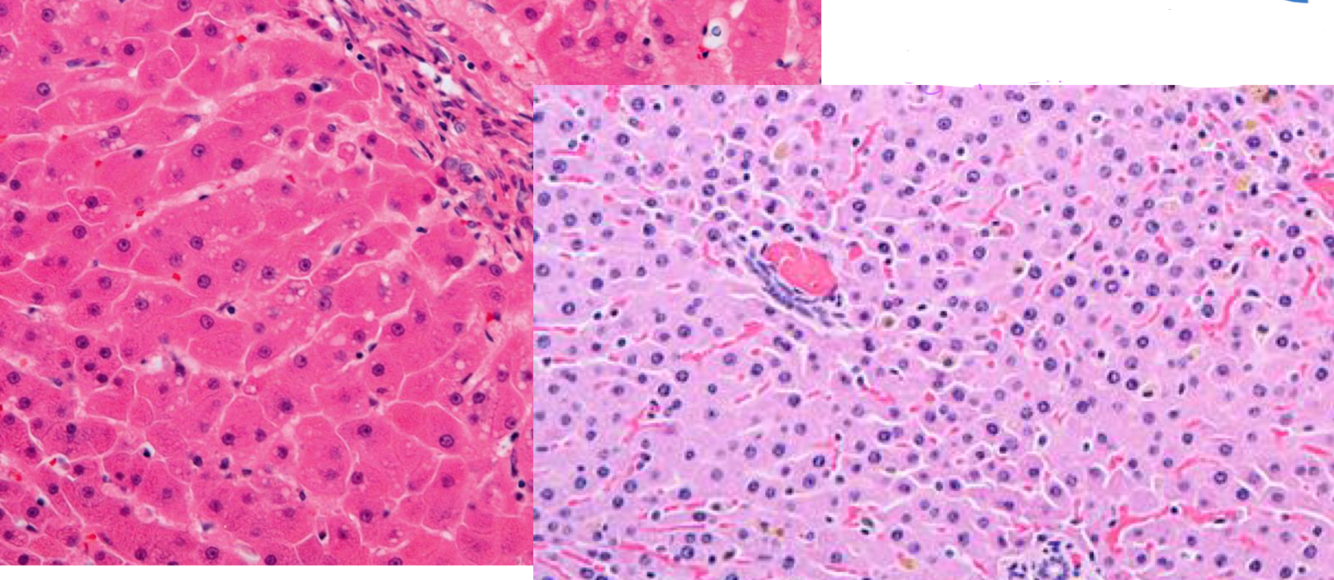

What can cause the reversible change seen in the liver specimen on the right?

Malnutrition/Starvation

*This is atrophy. Nuclei are the same size as the normal liver on the left, but cytoplasm is reduced.